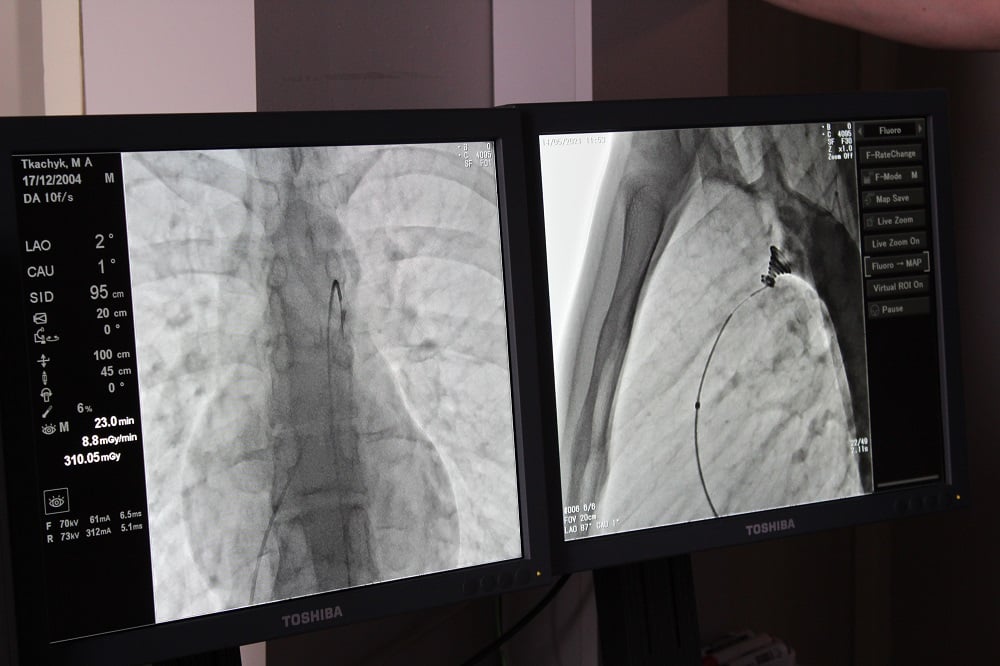

Вона була складною і проводилась під рентгенівським контролем із застосуванням ангіографа, під місцевим знечуленням (без наркозу). Через прокол у стегновій вені і артерії в незакриту протоку встановлено оклюдер (маленьку пружинку), яка перекрила потрапляння артеріальної крові у венозне русло.